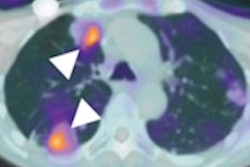

But the researchers posited that a recently developed visual interpretation method might find broader clinical use and make the radiopharmaceutical more available to clinicians. The method uses a color scale to represent counts of radiopharmaceutical uptake in the brain, and readers score brain regions as negative or positive based on an elevated flortaucipir signal of more than 65% above the cerebellar signal. The readers then are able to score whether brain regions have patterns of tracer uptake that either are or are not consistent with Alzheimer's disease.

Image displays categories used in the visual interpretation of flortaucipir PET scans. Three cases represent the three levels of visual reads and corresponding analysis end-point calculation. Image courtesy of JAMA Neurology.Baseline flortaucipir-PET scans showed that 240 subjects (66%) had patterns associated with advanced Alzheimer's disease, which presumably would them more susceptible to the disease. At the 18-month follow-up, 210 subjects (87%) maintained their advanced Alzheimer's pattern, with 147 (70%) of them having an increase of 1 point or more in their CDR, indicating their dementia had worsened.